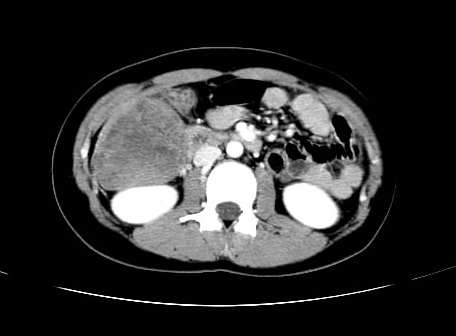

女 16岁  右上腹痛一天,无其他不适

肿块最大径位于十二指肠降段与水平段移行处,并且与肝脏压迹呈“0”形征,可以考虑位于肝外并与胃肠道关系紧密,考虑胃肠道间质瘤(gist)可能较大,须除外神经节起源肿瘤。

肿块与十二指肠关系密切,支持间质瘤诊断.肝脏与结肠均为受压改变.

右下腹巨大肿快,密度不均匀,内见坏死低密度区,边界清楚,与周边胀器明显有分界,未见强化,多考虑来源于间叶组织的良性肿物.

我坚决反对您的观点,该病例定位:横结肠肝曲与升结肠之间的肠系膜及部分肠壁。请看下图:

病灶巨大,少部分向肠腔内生长,大部分向长腔外生长。其密度不均匀,增强显示明显不均匀强化,并见有大片状始终不强化的不规则坏死液化区。虽然病灶中上部形态尚可,病人又如此年轻,但中下部形态、密度、强化特点强烈提示为恶性病灶。综上,我考虑本病例为:恶性胃肠道间质瘤。